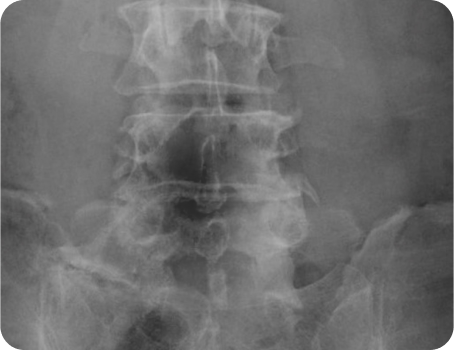

척추관 협착증

척추관이란 척추 중앙에 터널처럼 나 있는 파이프 구조를 말하고, 안이 비어있어 뇌로부터 팔다리까지 신경이 지나가는 통로가 됩니다.

추간공이란 추골과 추골 사이에서 척수 신경이 빠져나오는 공간을 뜻합니다.

척추관 협착증은 인대가 두꺼워지거나 뼈가 자라면서, 척추관이나 추간공이 좁아져서 생기는 질환이며 신경을 자극하여 염증과 통증이 나타나게 됩니다.

원인

• 뼈, 인대 등 척추관 주변 구조물의 퇴행성 변화

• 추간판 탈출증 및 추간판 후면의 비대

• 척추 골관절염, 척추후관절 골극형성

• 황색인대가 두꺼워짐

• 척추전방전위증, 후종인대골화증 등의 병변

• 척추에 무리를 주는 생활습관